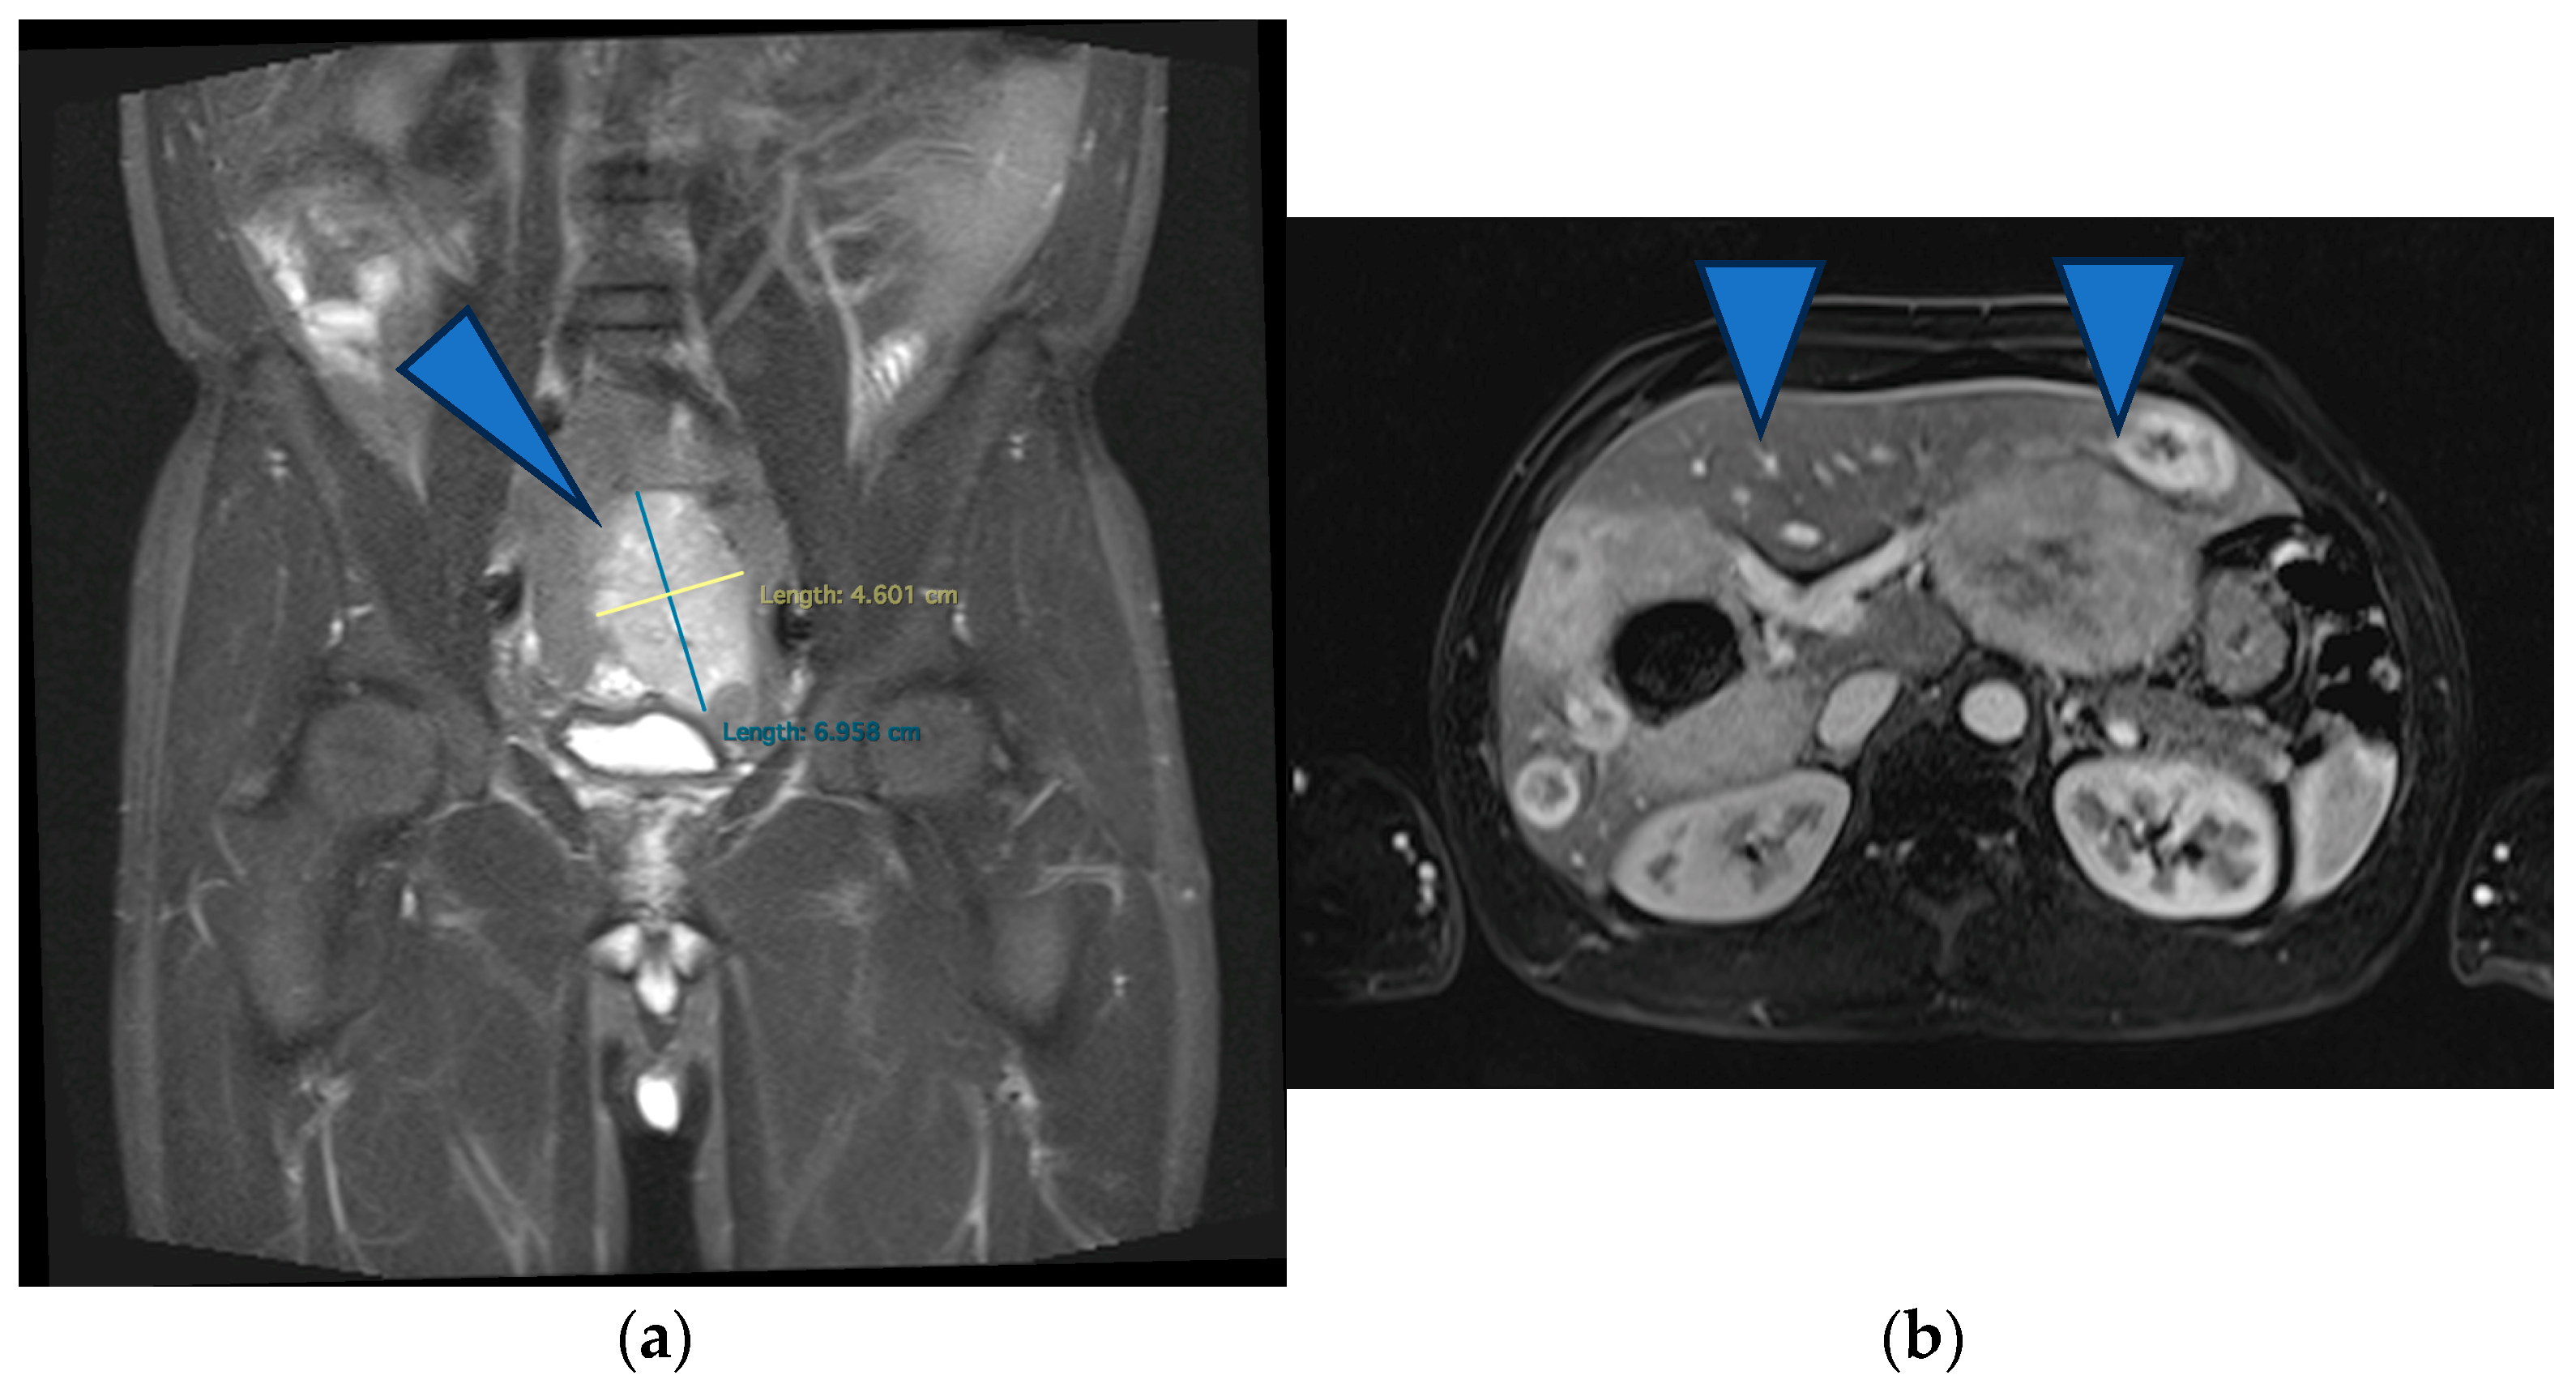

Figure 2.

(a) MRI showing stable disease according to the Choi criteria of the primary tumor (arrowhead) (b) and of the liver metastases (arrows).